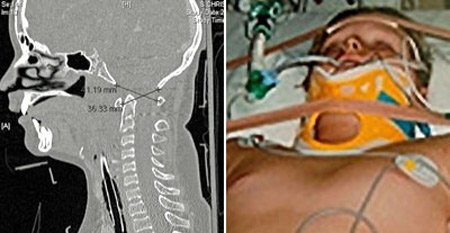

وتعرض ستيوارت إلى الحادث خلال مشاركته في سباق سيارات للناشئين، وهو الحادث الذي أسفر عن حدوث انفصال فقرات العنق عن الجمجمة. واعتقد الأطباء آنذاك أن ستيوارت سيموت حتما بعد انفصال عنقه عن جمجمته لكنه ظل على قيد الحياة واستجاب للعلاج تدريجيا.

وعقب حصول الحادث في أواخر العام 2006، قام الأطباء بإخضاع الصبي المصاب إلى عملية جراحية عاجلة استمرت لمدة 7 ساعات، وهي العملية التي نجحوا خلالها في إعادة تثبيت فقرات رقبته وتوصيلها إلى قاعدة الجمجمة باستخدام مسامير وشرائح مصنوعة من معدن التيتانيوم.